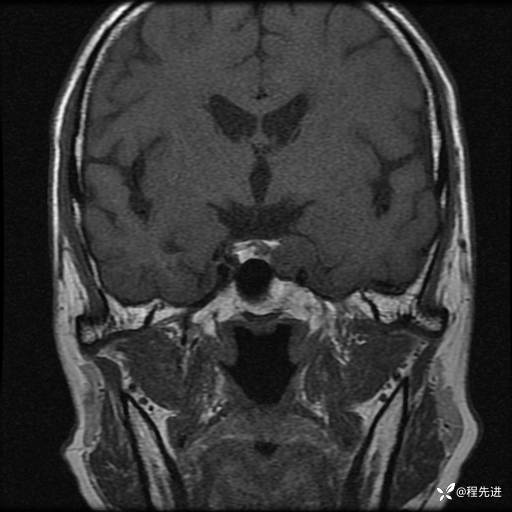

患者性别:男

患者年龄:74岁

简要病史:出现视物重影2月余,未予重视,2月来症状逐渐加重

MRI平扫+增强:

T1增强: